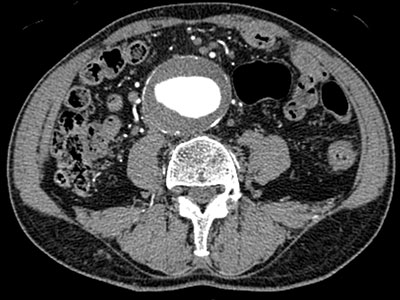

X線を用いて、人体の輪切り画像を作成し、体内の様々な情報を得ることができます。画像データから任意断面像やカラー3次元画像、血管像などを作成することも可能です。近年の技術進歩により、短時間、高精細、低被ばくの検査が可能です。当科でも最新のDual Source CTを導入し診療を行っています。また、IVRでは、画像誘導下生検や椎体形成術等、正確な位置情報に基づいた精緻な手技にも用いられます。

造影CTおよび3D画像